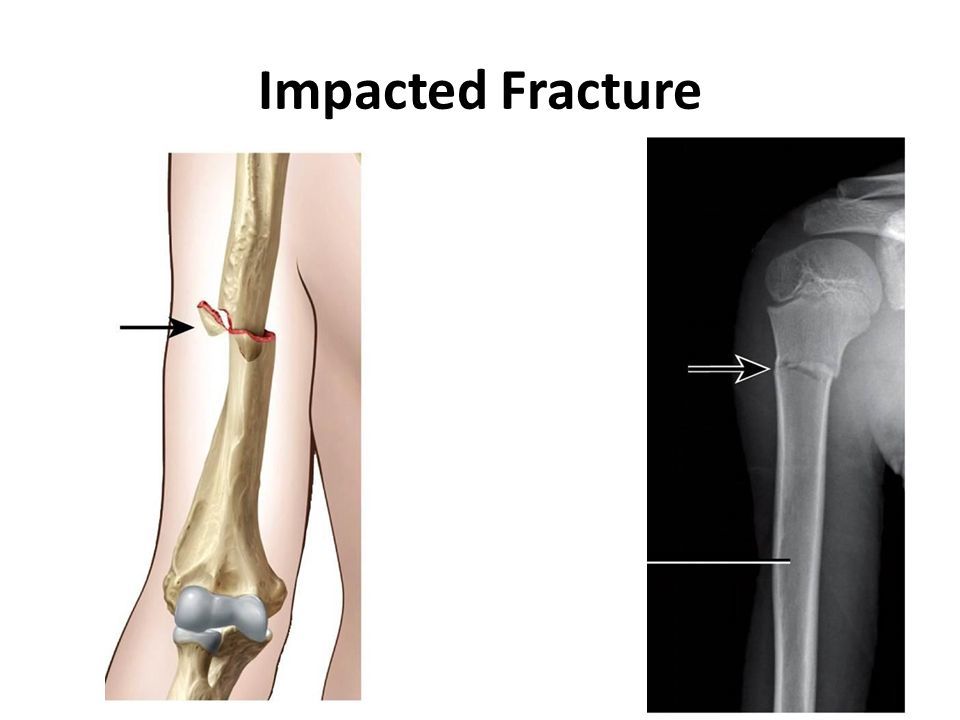

What is an impacted fracture?

Axial force through the bone impacts the two bone ends together, so the bone appears sclerotic